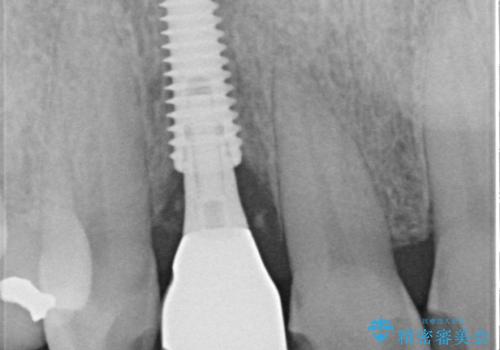

仮歯を事前に用意し、インプラント埋入時に即日で仮歯を装着する、即時荷重インプラントの計画で治療を進めて行くこととしました。

新幹線や飛行機を利用しても来院であり、極力来院回数を減らしたり、東京に用事があるタイミングに合わせてアポイントを調整したりと、負担が少なくなるようにして治療を進めて行きました。

来院間隔があいたため、予定よりも長くなりましたが、大きなトラブルもなく、外科処置は1回のみ、最小の来院数で無事に治療を終えることができました。